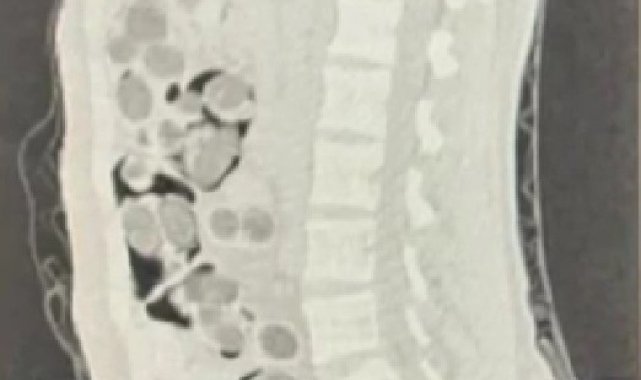

Denizli İl Emniyet Müdürlüğü Narkotik Suçlarla Mücadele Şube Müdürlüğünce, uluslararası uyuşturucu madde ticaretinin önlenmesine yönelik çalışmalar devam ediyor. İstanbul'dan bindiği uçakla Denizli Çardak Havaalanına gelen yabancı uyruklu bir kişi uyuşturucu madde taşıma şüphesiyle takibe alındı. Yapılan takibin sonucunda şüphelinin yurt dışından getirdiği uyuşturucu maddeleri teslim edeceği kişiyle buluştuğu sırada operasyon düzenlendi. Operasyon sonucunda iki yabancı uyruklu şüpheli gözaltına alındı. Uyuşturucu madde kuryesi olan şüpheli şahsın üzerinde yapılan iç beden muayenesinde doğal yollarla yutmuş 177 paket halinde toplamda 1 kilo 144 gram skunk maddesi, 38 paket halinde 178 gram metamfetamin maddesi, 3 paket halinde 90 adet uyuşturucu hap, 1 paket halinde 7 gram Afyon sakızı maddesi olmak üzere toplam 219 paket uyuşturucu ve uyarıcı madde ele geçirildi.

Midesinde 219 paket uyuşturucu madde taşıdığı tespit edilen uyuşturucu kuryesinin hastanede müşahede altına alındığı, hastanede 5 gün müşahede altında kaldığı süre boyunca 219 paket uyuşturucu maddenin doğal yollarla midesinden çıkartıldığı ifade edildi. Hastanede işlemlerinin ardından uyuşturucu veya uyarıcı madde ticareti yapmak suçundan adli makamlara sevk edilen yabancı uyruklu kurye ve yine yabancı olan zehir taciri tutuklanarak cezaevine gönderildi.